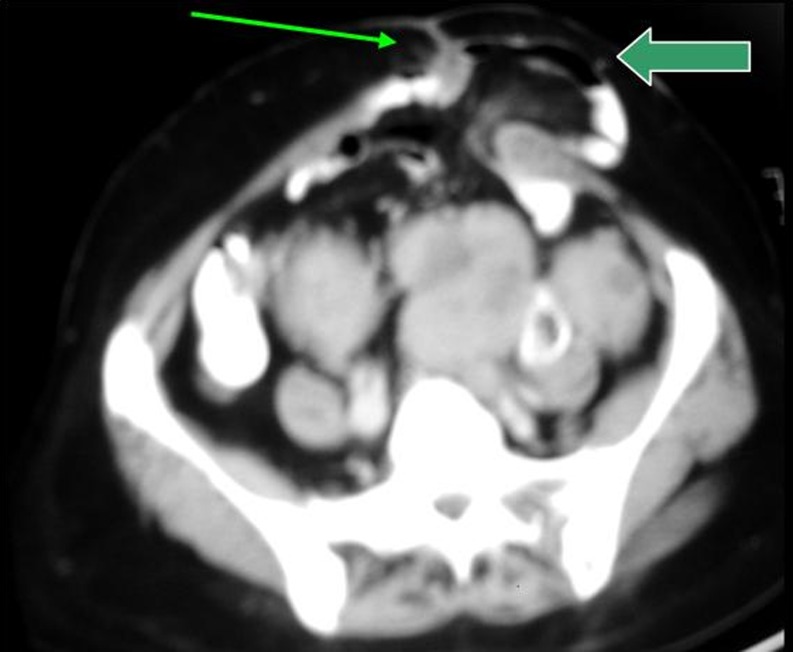

Lumbar Hernia

Lumbar hernias are uncommon hernias [23]. They can be congenital [24] or can occur after surgery [23], blunt trauma, or fracture or partial surgical resection of the illium [25]. They occur in the posterior flank through defects of the lumbar muscles and aponeurosis, located below the 12th rib, above iliac crest, posterior to the erector spinae muscle in the superior (Grynfeltt-Lesgaff) lumbar triangle or inferior (petits) lumbar triangle (Fig. 7). CT easily demonstrates lumbar hernia in obese patients and postoperative patients [26].

Fig. 7.

Lumbar hernias. CT scan shows mesenteric fat and collapsed large bowel loop in the left posterolateral part of the abdominal wall, through lumbar triangle (arrow)